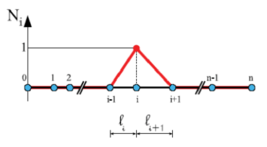

From the methodology point of view, a new methodology to compute diagnostic indicators based on computational hemodynamics has been proposed. In order to compute the pressure drop under different patient-specific situations, a reduced-order model has been developed in paper 1. The reduced-order method was implemented as part of the C++ finite element library KRATOS[61]. KRATOS is a multiphysics simulation open source (LGPL licence) framework based on the stabilized Finite Element Method for analysis of the Navier-Stokes equations in viscous flows. Efficient and parallel solvers for 3D fluid problems have been implemented in KRATOS that allow tackling large problems using supercomputers if available. The 1D model developed in this monograph was also implemented as new elements inside KRATOS. Blood was modeled as a Newtonian fluid with constant density and different outlet conditions were implemented. In appendix 9 a detail description of the implementation is shown.

Boundary conditions from multiscale modeling of circulation: Another approach to impose the boundary conditions is to use reduced models, as 1D model or 0D (lumped) models. 1D and 0D models are mathematical models able to reproduce the systemic and pulmonary circulation. Figure 10 shows a standard approach to provide realistic local boundary conditions for 3D CFD simulations at the specific arterial domain using 1D models of the entire arterial tree and 0D models at the distal ends[83]. 1D model solves the Navier-Stokes equations under some assumptions (see appendix 9) and lumped models (0D models) can be derived from electrical circuit analogies where blood flow is represented by the current and arterial pressure by the voltage. Usually the electrical components of these circuits are resistances, inductances and capacitors. Where resistances represent arterial and peripheral resistance that occur as a result of viscous dissipation inside the vessels, capacitors represent volume compliance of the vessels that allows them to store large amounts of blood, and inductors represent inertia of the blood[75]. The values of these electrical components can be estimated from physical data of the subject [84][85]. This approach is quite used because it is capable to account for the effect of local pathological conditions on the whole circulatory system, providing realistic boundary conditions for the 3D problem [75][79][86].